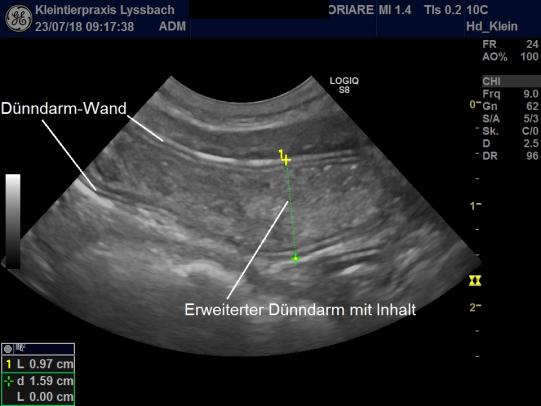

Im Ultraschall findet sich eine abnormale Struktur: Der Dünndarm scheint sich auf einem kurzen Abschnitt zu erweitern und von einer weiteren Struktur ausgefüllt zu sein, welche sonografisch ebenfalls als Darm identifiziert werden kann. Offensichtlich handelt es sich bei dieser "Bull's Eye"-Struktur um eine sogenannte Invagination: Wie ein Strumpf hat sich der Dünndarm an dieser Stelle in sich selbst hinein eingestülpt, blockiert nun das Darmrohr und bewirkt dadurch einen Darmverschluss.